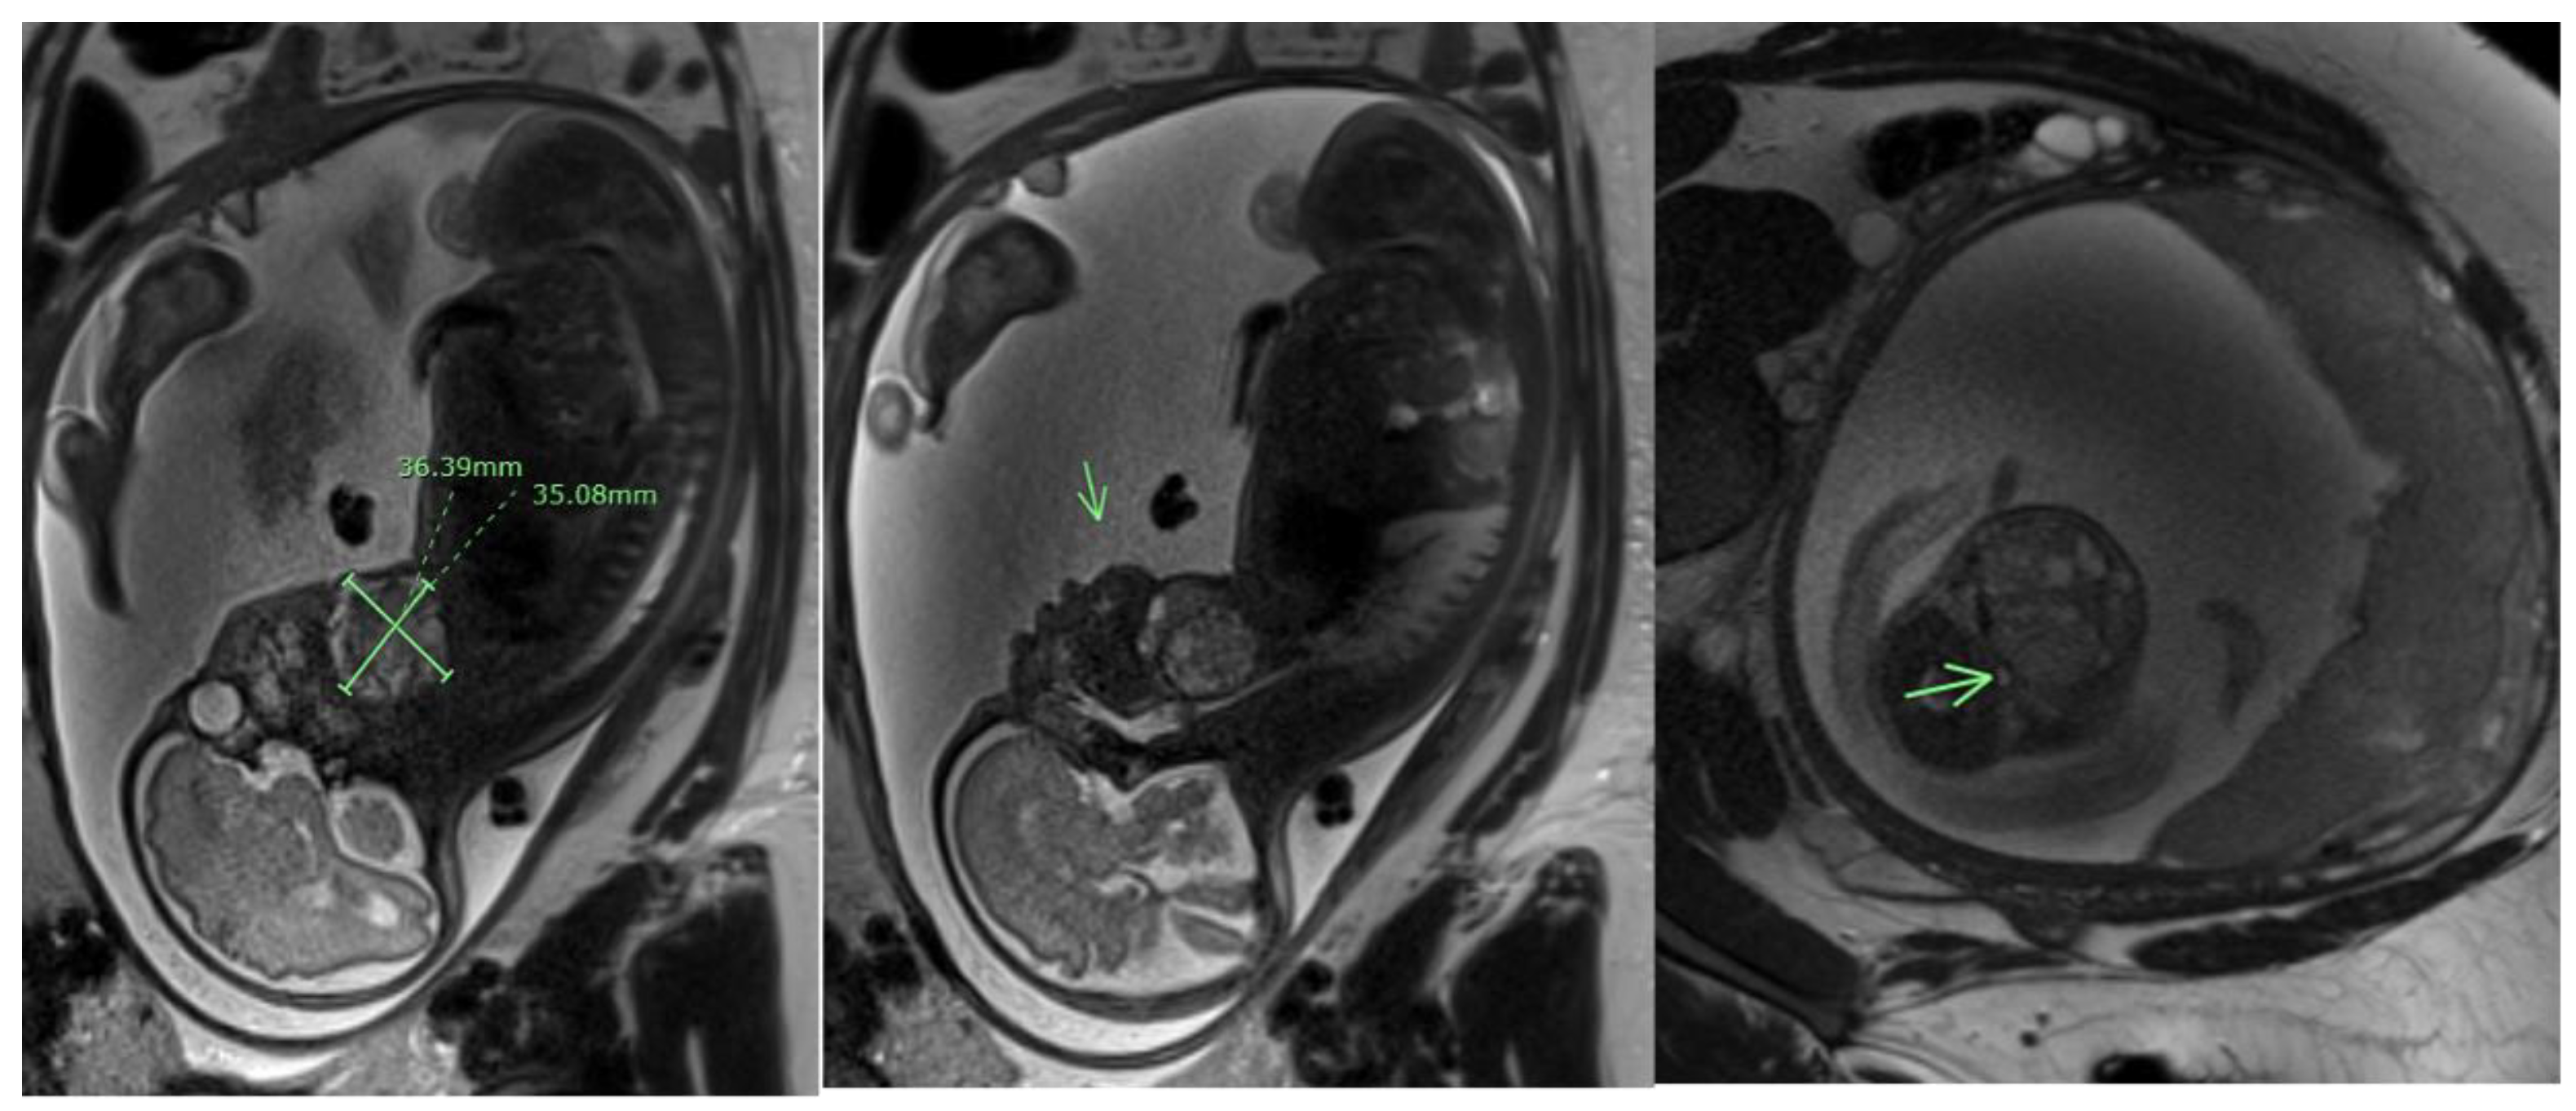

Similarly to SCTs, most head and neck teratomas are detected during routine sonography in the late second and third trimesters [68,69]. A comprehensive prenatal evaluation is essential for prenatal counseling and management of these patients. On ultrasound, these teratomas typically present as an anterior or bidirectional facial or cervical mass, which may be partially solid or cystic [69,70]. The mass can protrude and cause the hyperextension of the fetal head, with severe perinatal sequelae if left untreated. Three-dimensional ultrasound has proven useful in enhancing prenatal diagnosis and aiding in the delivery planning of these patients [71]. Additionally, fetal MRI (Figure 5) enhances the diagnostic accuracy of the prenatal diagnosis, providing important information regarding the anatomy of the airway [72,73]. Prenatal imaging is also necessary in ruling out associated structural anomalies that may direct to the etiology. Finally, genetic analysis is required for all prenatally diagnosed teratomas to properly identify associated congenital abnormalities [6,74,75].

Figure 5.

Fetal MRI of a cervical teratoma at 29 weeks and 1 day of gestation. Arrows point to the cervical teratoma.